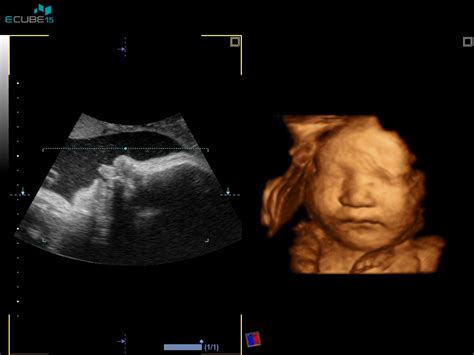

Pomemben del njene prakse je tudi področje prenatalne in postnatalne diagnostike. Kot ustanoviteljica ambulante Medgen, s pridobljenimi izkušnjami iz Lyonu (Francija) in Ženeve (Švica), je dr. Tul Mandićeva ključna pri izvajanju genetskih posvetovanj. V Sloveniji je uvedla in uspešno razširila prakso prenatalne diagnostike kromosomskih in strukturnih nepravilnosti pred rojstvom. Skoraj 90 odstotkov nosečnic v Sloveniji opravi ta pregled ploda že v 12. tednu nosečnosti, kar omogoča zelo učinkovito odkrivanje Downovega sindroma in drugih nepravilnosti, kot je mikrocefalija.